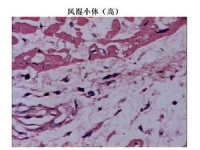

6、全身系统疾病:包括结缔组织病如:系统性红斑狼疮、结节性多动脉炎、风湿性关节炎、硬皮病和皮肌炎;浸润和肉牙肿如结节病及白血病;

② 肥厚性心肌病 特点为左心室或右心室肥厚,通常是非对称性,并侵及室间隔。典型者左心室容量正常家长或减低,常有收缩期压力阶差。家族性通常为常染色体显性遗传,本病由肌质网收缩蛋白基因突变所致。典型形态学改变为心肌细胞肥大和排列紊乱,周围疏松结缔组织增多。多发生心律失常及早年猝死。